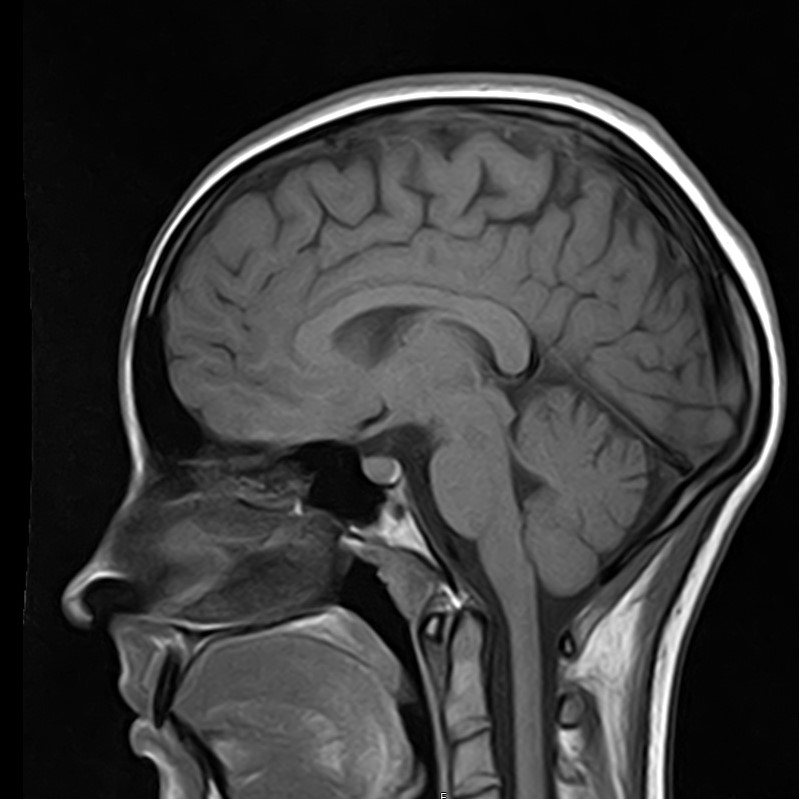

В клинике «Доступная медицина» можно пройти комплексное обследование, включающее в себя два протокола сканирования близко расположенных друг от друга анатомических областей – шейного отдела позвоночника и головного мозга.

Сканирование проводится на современном высокопольном магнитно-резонансном томографе закрытого типа TOSHIBA VANTAGE TITAN 1,5 Тесла, который делает послойные срезы в разных плоскостях с шагом от 1 мм и на основе полученных данных создает трехмерные изображения превосходного качества. Метод исследования позволяет в мельчайших подробностях визуализировать состояние всех структур головного мозга и шейного отдела позвоночника, что дает возможность выявлять патологические изменения на ранних стадиях и назначать своевременное лечение.